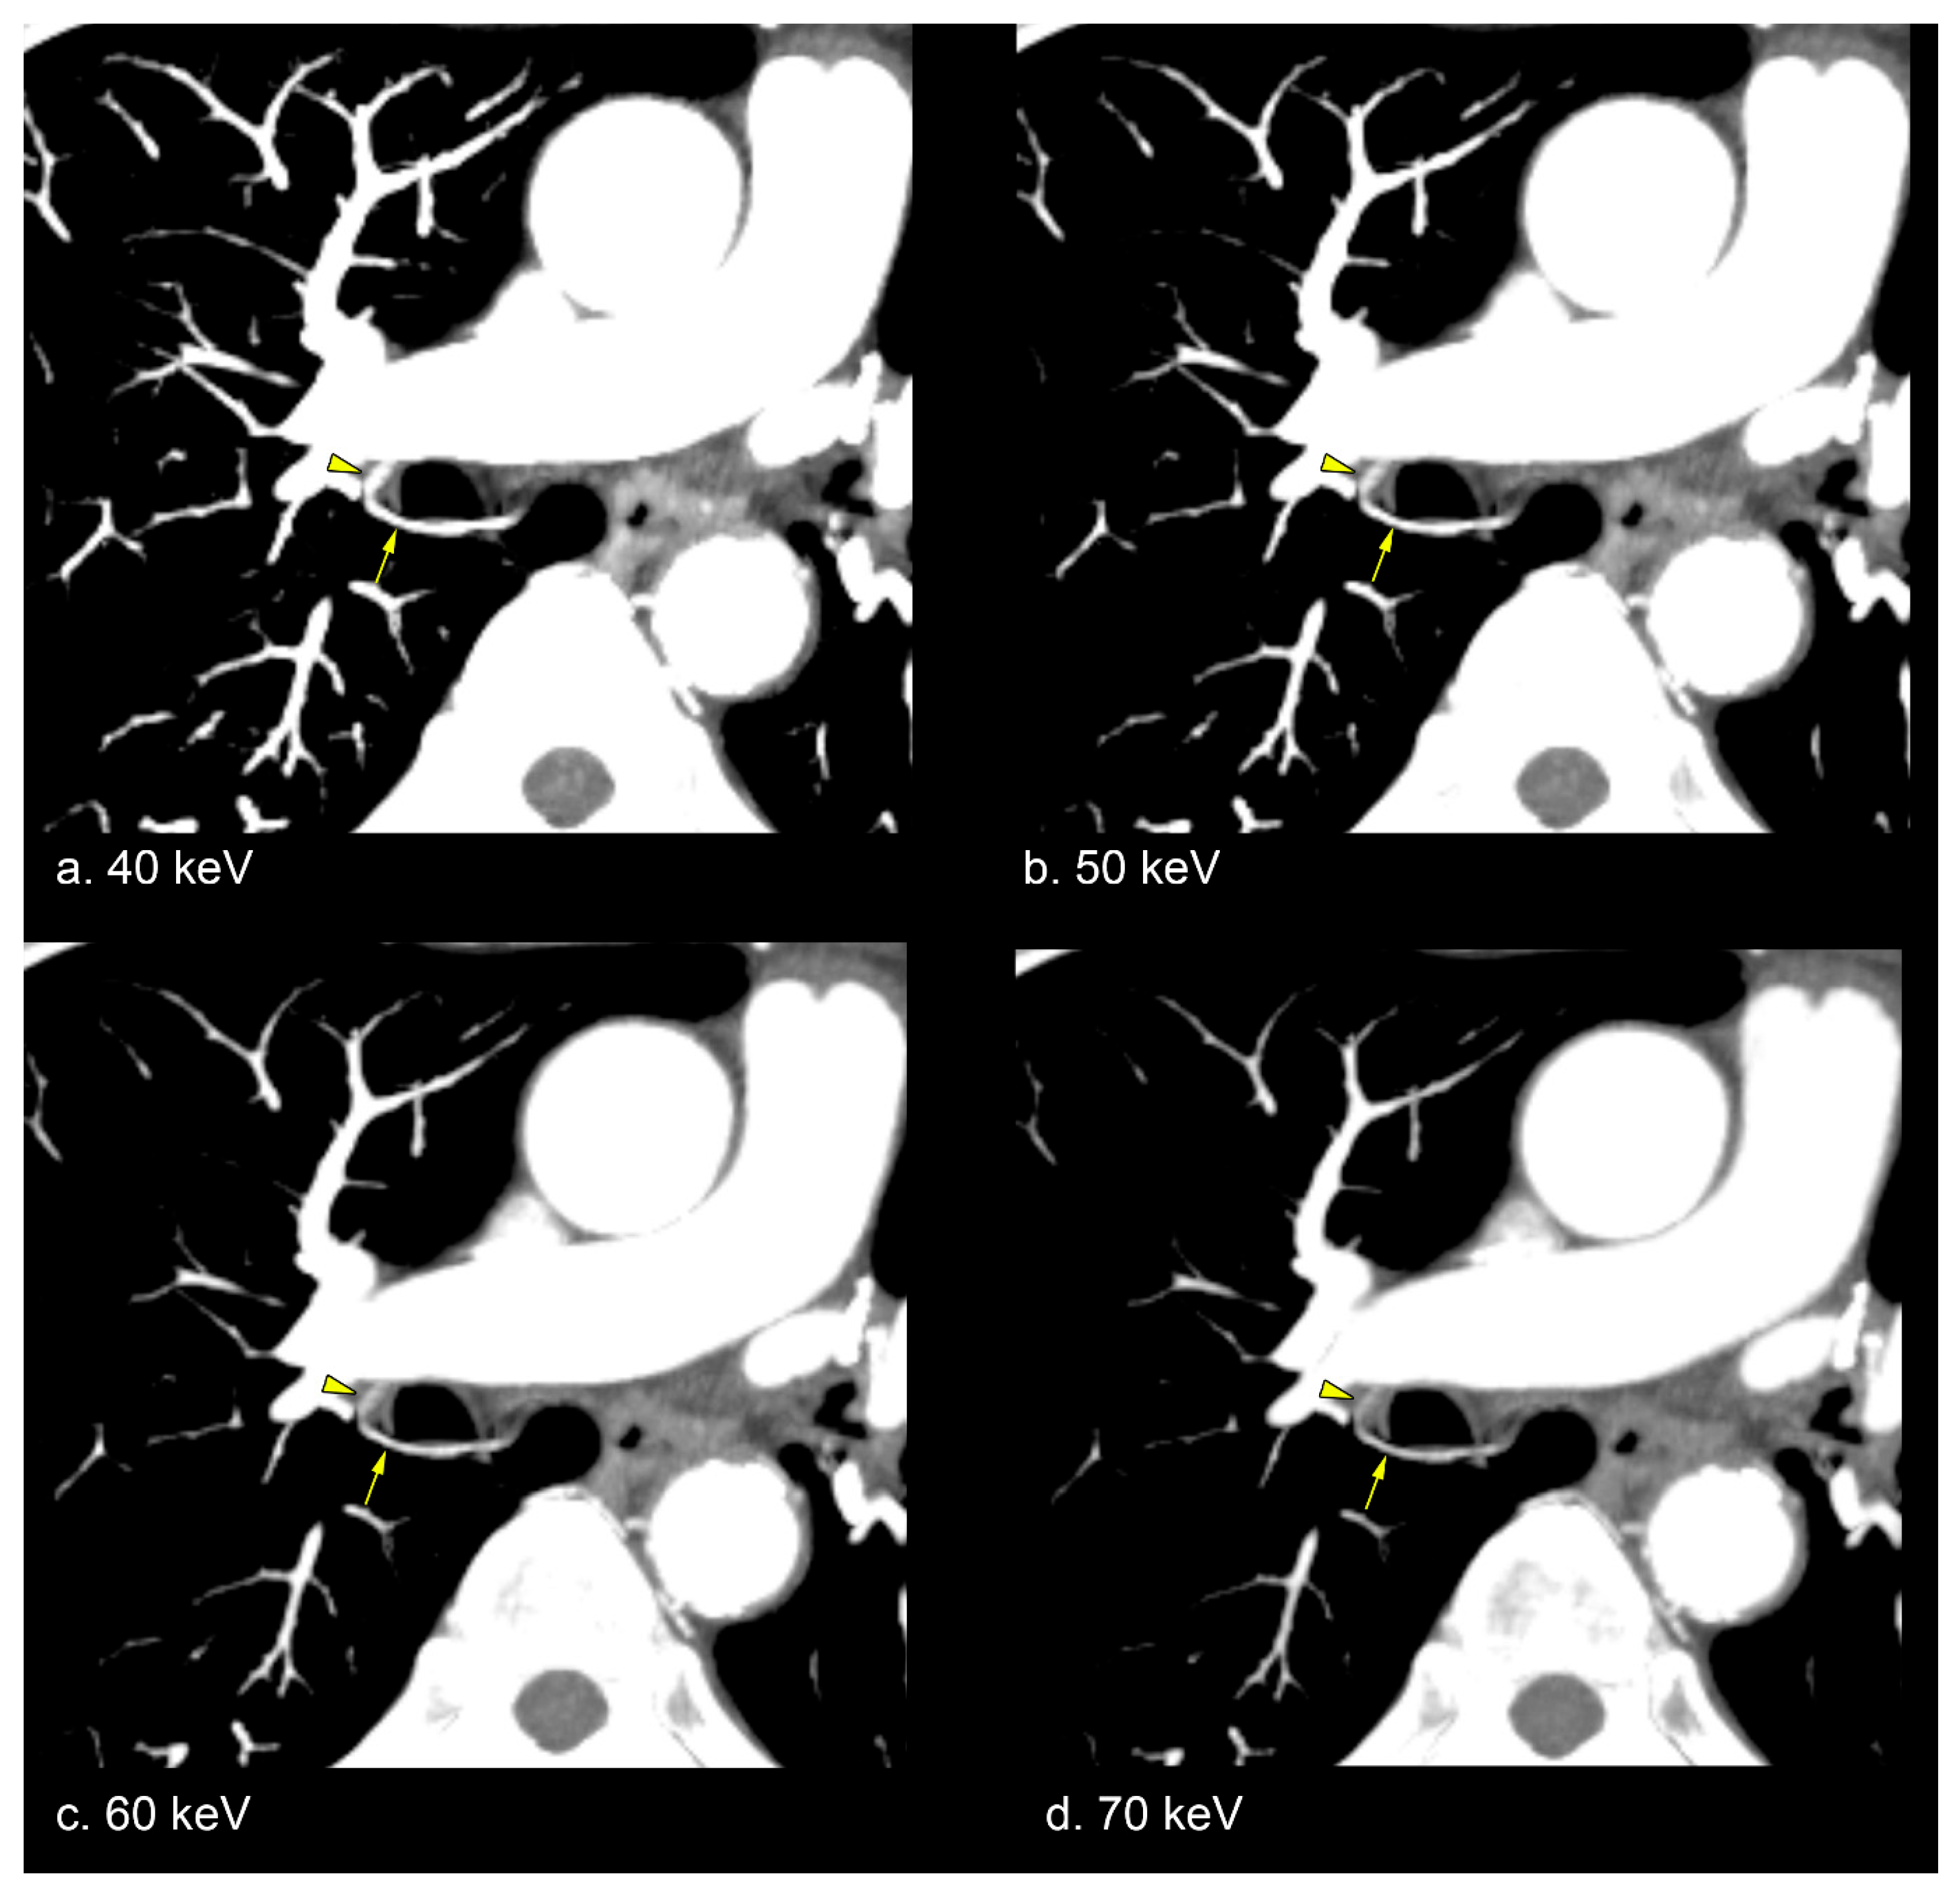

2.5. Representative Image